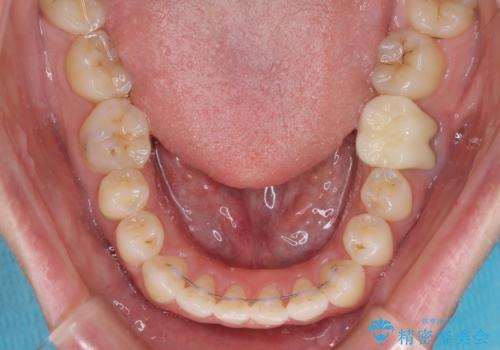

1年半程度の期間を見込んでいましたが、上下の真ん中の位置をできる限り合わせるための調整に少し時間がかかってしまいました。

咬み合わせが安定し、前歯の汚れも付きにくくなりました。